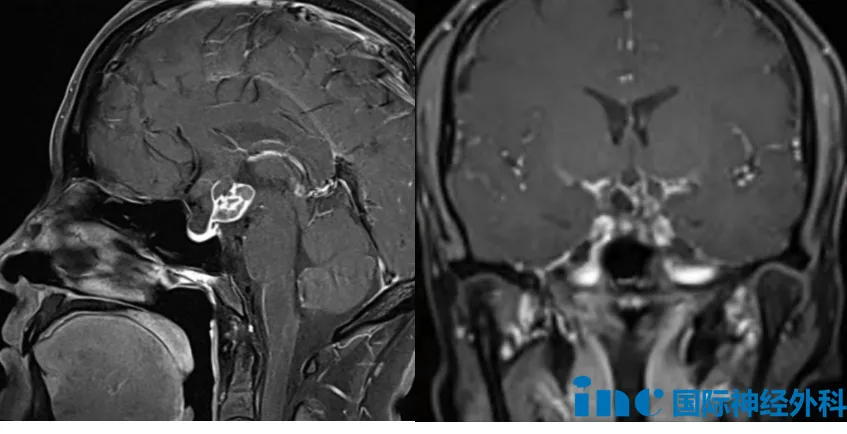

39岁的周女士,确诊为鞍区颅咽管瘤(病灶约1.9cm×1.8cm×2.3cm)。病程初期以继发性闭经为首发表现,经系统影像筛查发现鞍区占位,增强MRI确诊后辗转求医,却遭遇了不同医生在手术入路上的明显分歧——一方建议开颅,一方主张经鼻,诊疗决策陷入僵局。在深入了解到巴特朗菲教授在颅底肿瘤领域的国际学术地位与临床造诣后,周女士主动把握此次来华咨询的机会。